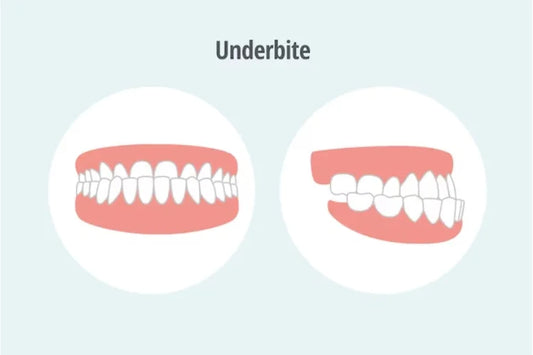

Underbite: What Causes It, Why It Matters, and ...

Table of Contents What is an Underbite? What Causes an Underbite? Genetics Childhood Habits Life’s Unexpected Turn: The Trauma Why Correcting an Underbite is Important Protect Your Teeth Say Goodbye...

Underbite: What Causes It, Why It Matters, and ...

Table of Contents What is an Underbite? What Causes an Underbite? Genetics Childhood Habits Life’s Unexpected Turn: The Trauma Why Correcting an Underbite is Important Protect Your Teeth Say Goodbye...